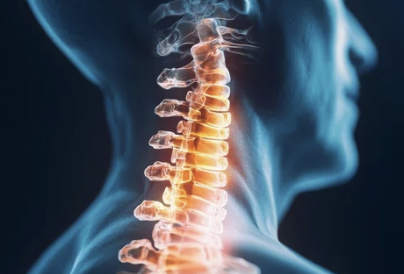

1. 목디스크란? 원인과 특징 이해하기

목디스크는 목뼈 사이에 위치한 디스크가 압박을 받아 탈출하거나 손상되어 발생하는 질환이에요. 디스크가 탈출하면서 신경을 누르게 되어 통증과 다양한 증상이 나타납니다.